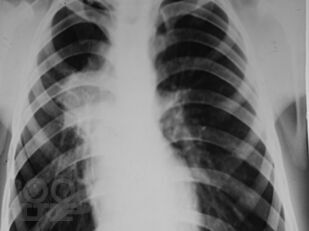

Рентгенологические синдромы при туберкулезе органов дыхания

В предлагаемом учебно-методическом пособии рассматриваются основные рентгенологические синдромы при патологии органов дыхания, а также частные вопросы рентгенологической диагностики туберкулеза органов дыхания.